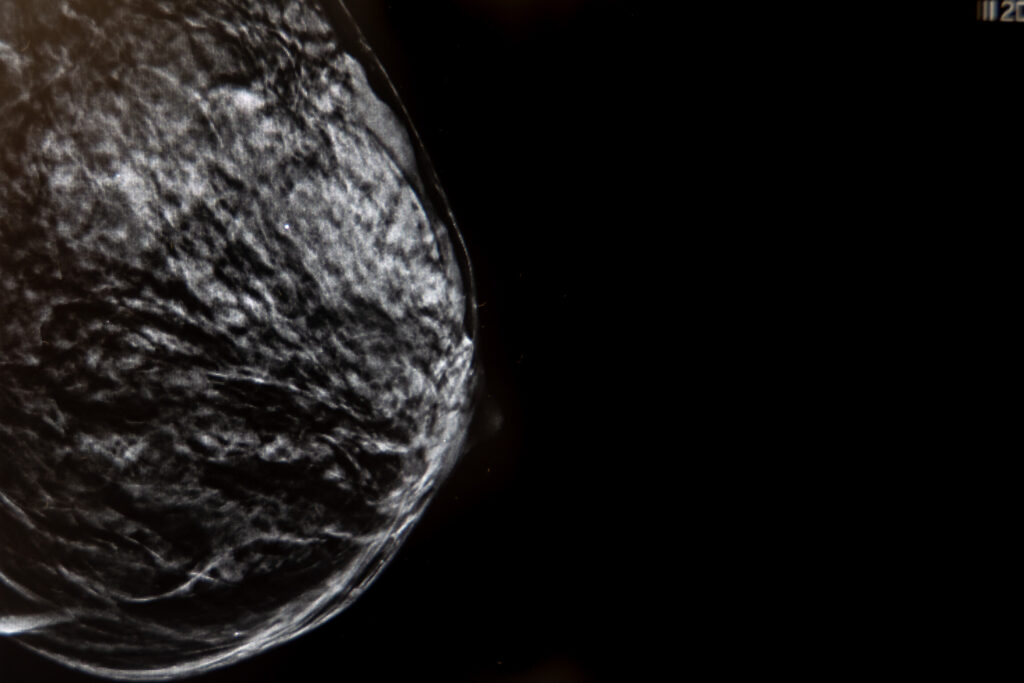

La mamografía con tomosíntesis, también conocida como mamografía 3D, es una técnica avanzada de imagen mamaria que utiliza rayos X de baja dosis para crear una imagen tridimensional de la mama. A diferencia de la mamografía tradicional, que proporciona una imagen bidimensional, la tomosíntesis captura múltiples imágenes desde diferentes ángulos, permitiendo una visualización más detallada del tejido mamario.

- Detección de cáncer de mama: permite identificar tumores pequeños que podrían pasar desapercibidos en una mamografía convencional, especialmente en mamas con alta densidad de tejido.

- Mayor precisión en mamas densas: reduce la superposición de los tejidos, mejorando la visualización de las estructuras mamarias en mujeres con mamas densas.

- Imágenes 3D: proporciona una visualización tridimensional de la mama, permitiendo una mejor detección de lesiones.

- Detección de lesiones ocultas: ayuda a detectar lesiones que podrían estar ocultas en una mamografía tradicional.